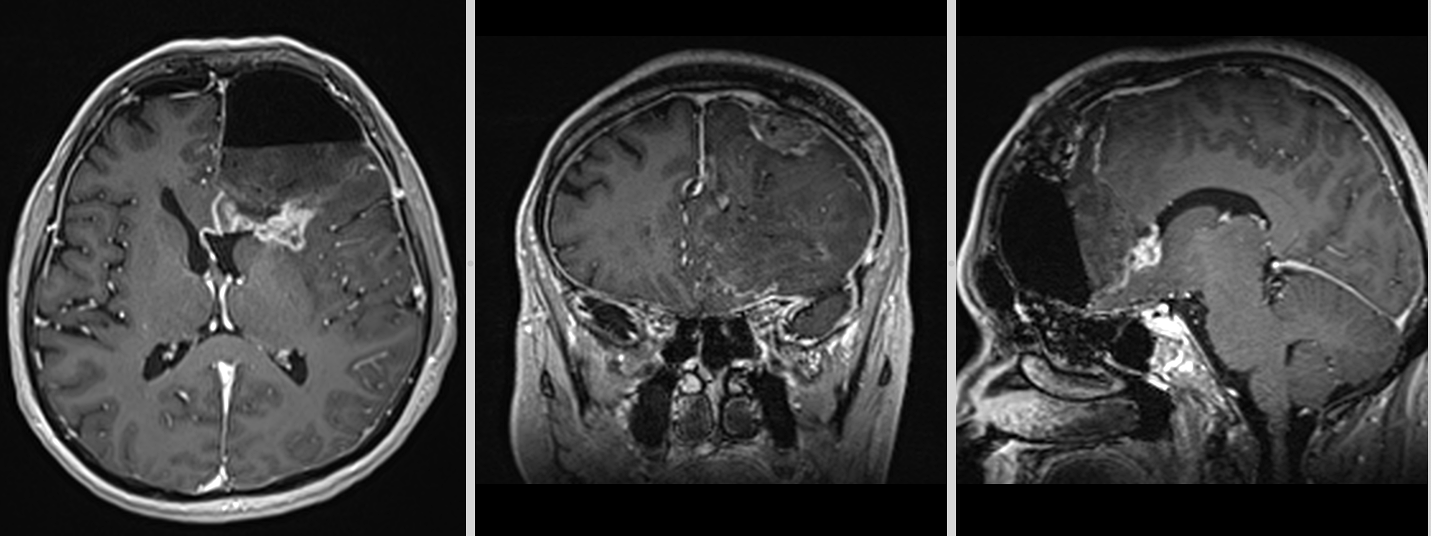

Recidiva – inevitabilitate biologică

Recidiva nu este o eventualitate, ci o etapă a evoluției bolii.

Aceasta apare de obicei:

- în vecinătatea cavității de rezecție

- rar, la distanță

La momentul recidivei, tumora este adesea:

- mai rezistentă

- mai heterogenă

- mai dificil de tratat

Etapa 3 – Controlul RMN (cu contrast)

- Primul RMN postoperator – la 24 ore de la operație.

- Al doilea RMN – la 3 săptămâni de la operație (va fi folosit și pentru planul de radioterapie).

- Al treilea RMN – la 6 săptămâni de la încheierea radioterapiei.

- Următoarele RMN – la interval de 2 luni.

Etapa 7 – Recidiva

- Tratamentul în caz de recidivă trebuie particularizat în funcție de situația concretă și stabilit în cadrul unei comisii multidisciplinare formate din neurochirurg, radioterapeut și oncolog.

- Reintervenția chirurgicală – atunci când recidiva este pe locul fostei tumori sau în vecinătate (nu la distanță sau în emisferul cerebral contralateral).